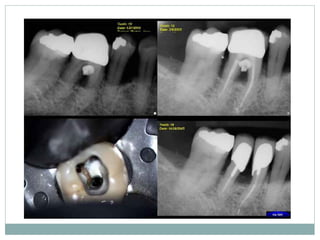

Hemisection

 It is splitting of a two-rooted tooth into two separate

portions

 This process has been called bicuspidization or

separation as it changes the molar into two

separate roots.

 It is most likely to be performed on mandibular

molars with buccal and lingual class II or III

furcation involvements

Tunnel preparation